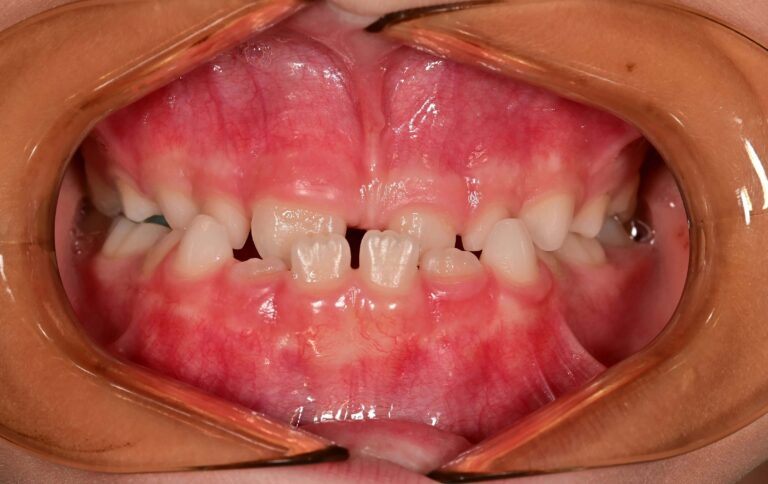

Отворена захапка

Отворената захапка вид малоклузия, при която горните и долните зъби не се докосват, когато устата е затворена. Отворената захапка може да засегне както предните, така и задните зъби.

Предна отворена захапка – при нея задните зъби се докосват, горните и долни предни зъби не се припокриват. Често това се дължи на вредни навици по време на ранното детство, като смучене на палеца, неправилно позициониране на езика или дишане през устата по време на ранното развитие на зъбите.

Задна отворена захапка – При нея предните зъби се срещат, докато задните остават отворени.

Усложнения, които могат да настъпят – Отворената захапка причинява проблеми с преглъщането, проблеми с говора, затруднения при дъвченето и отхапването. При предната отворена захапка силната захапка върху задните зъби без опората на предните води до по-голям риск от проблеми с венците и фрактури.